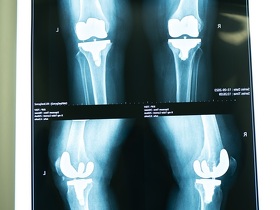

Эндопротезирование – это операция, во время которой хирург вместо естественного сустава устанавливает его искусственный, гипоаллергенный протез, устраняя разрушенные заболеванием или травмой ткани. Это позволяет избавить пациента от ограниченности движений, болезненных ощущений, уберечь от инвалидизации. К такому методу прибегают при значительных повреждениях сустава или дегенеративных изменениях из-за заболеваний:

В Клинике МЕДИКОМ на Оболони проводятся операции 1 и 2 категорий сложности по замене суставов:

- коленного;

Как проводятся операции по эндопротезированию суставов